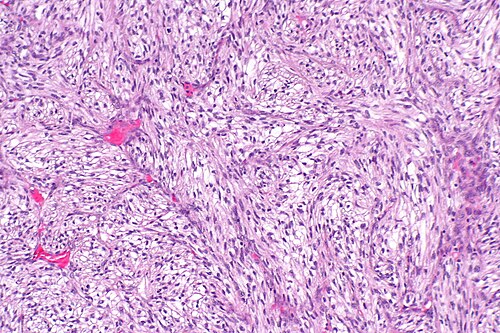

1

Diagnosis?

Sarcomatoid differentiation in renal cell carcinoma -- intermed mag.jpg

Angiomyolipoma

Benign kidney

Chromophobe renal cell carcinoma (classic)

Chromophobe renal cell carcinoma (eosinophilic)

Clear cell papillary renal cell carcinoma

Clear cell renal cell carcinoma

Collecting duct carcinoma

Cystic nephroma/mixed epithelial stromal tumour

HLRCC syndrome associated RCC

Hybrid oncocytic/chromophobe tumour

Metastatic carcinoma

Mucinous tubular and spindle cell carcinoma

Oncocytoma

Papillary renal cell carcinoma

Renal cell carcinoma, unclassified

Renal medullary carcinoma

Succinate dehydrogenase-deficient renal cell carcinoma

t(6;11) translocation carcinoma

Tubulocystic renal cell carcinoma

Urothelial carcinoma

Wilms tumour

Xanthogranulomatous pyelonephritis

Xp11.2 translocation carcinoma